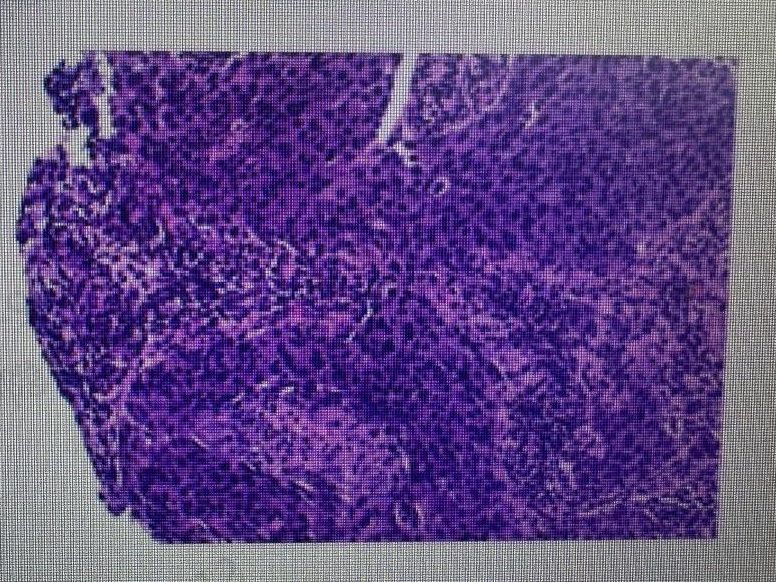

• 穿刺病理:

右乳病理诊断:右乳浸润性癌(非特殊型,组织学分级III级)

免疫组化:ER约5%弱(+),PR(-),C-erbB-2(3+),Ki-67热点区约60%(+),GATA-3(+),P63(-),CK5/6(-)

右腋下病理诊断:右腋下,乳腺癌转移

免疫组化:ER(-),PR(-),C-erbB-2(3+),Ki-67热点区约60%(+),GATA-3(+)

图4 右侧肿块穿刺病理(2024-03-04)